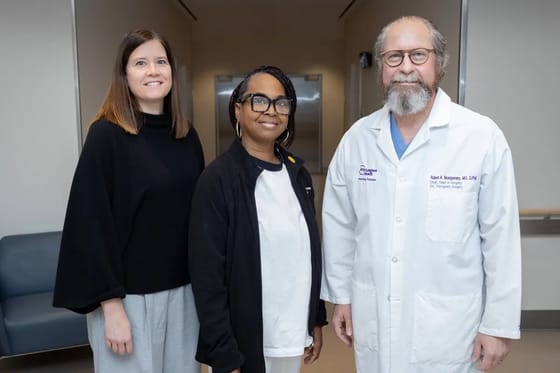

Óriási orvosi siker: két hónapja él génmódosított sertésvesével egy amerikai nő, és jól érzi magát

Áttörést jelenthet a xenotranszplantációban annak az amerikai nőnek az esete, akit még 2024 novemberében műtöttek meg New Yorkban, hogy génmódosított sertésvesét kapjon. Hamarosan Alabamába is hazatérhet.